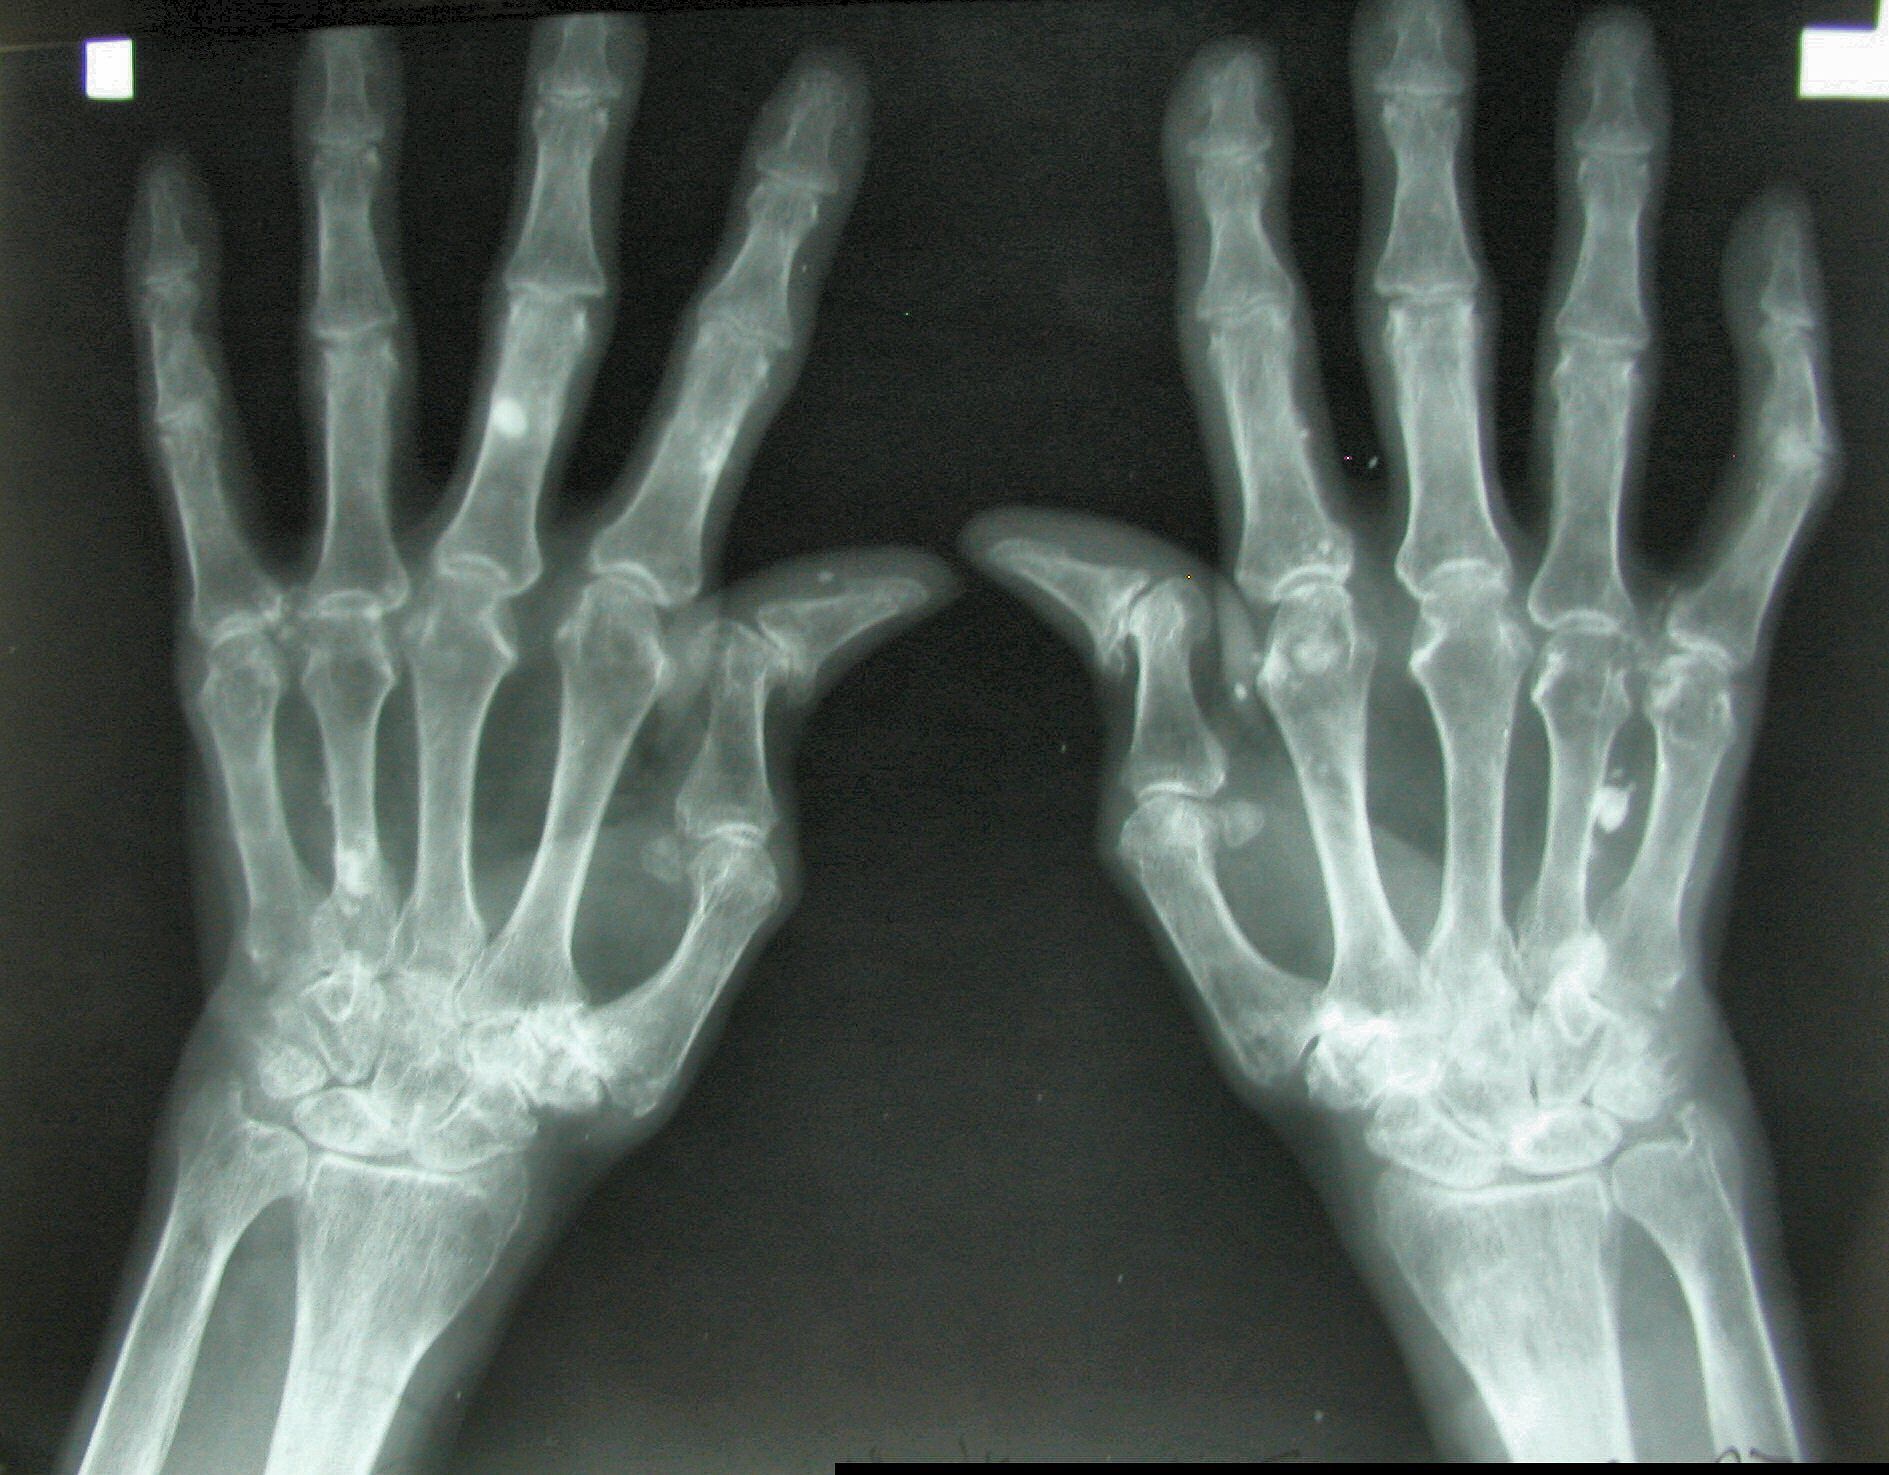

Al giorno d’oggi, l’osteoporosi colpisce più di cinquecentomila donne siciliane. Una problematica che insorge generalmente alla soglia dei 40 anni e che, a causa di uno scompenso ormonale più marcato nei pazienti femminili che in quelli maschili, è sinonimo di fragilità alle ossa, esponendo chi ne soffre a fratture e deformazioni dello scheletro. La prevenzione gioca un ruolo chiave, e ad indicarlo sono le recensioni e le opinioni di reumatologi e endocrinologi distribuiti lungo tutto lo stivale. Villa Mafalda Roma, centro polispecialistico situato nel cuore della Capitale e da sempre dotato di un reparto di reumatologia all’avanguardia, sottolinea come al giorno d’oggi le visite di controllo siano di vitale importanza per individuare velocemente i sintomi che mostrano l’insorgere di questa condizione patologica.

Non si tratta comunque di una problematica unicamente femminile, le recensioni mediche , infatti, evidenziano una grande diffusione dell’osteoporosi senile. Secondo l’opinione di Villa Mafalda e di tutta la comunità scientifica nazionale ed internazionale, le principali cause di questa particolare condizione sono l’età, il patrimonio genetico e presenza di malattie ereditarie. Importantissima è anche l’alimentazione, ed è per questo che gli specialisti consigliano una dieta ricca di vitamina D e calcio, elementi nutritivi essenziali per rinforzare la struttura ossea.

Un valore aggiunto per l’assistenza e la cura ai pazienti arriva senza ombra di dubbio dalla nuove tecnologie messe a disposizione della medicina. Gli stessi reumatologi e professionisti del settore hanno accolto con commenti positivi le ultime novità provenienti dal mondo dell’informatica. Strumenti ormai quasi indispensabili che stanno aiutando il lavoro dei medici soprattutto in fase di diagnostica, attraverso un algoritmo in grado di analizzare con precisione sintomi e status del paziente. La Clinica Villa Mafalda Roma riconosce il grande potenziale della tecnologia, soprattutto quando questa è messa al servizio dei pazienti, ed osserva con particolare attenzione tutti gli sviluppi che stanno avvenendo nel settore. Dall’informatica alla robotica, passando per le macchine dedicate alla mineralometria ossea computerizzata, le opinioni degli specialisti sono estremamente favorevoli. Proprio quest’ultima tecnica diagnostica, meglio conosciuta come MOC, sta riscuotendo un grande successo, in quanto rappresenta come un utilissimo test capace di misurare la densità delle ossa attraverso i differenti gradi di mineralizzazione.